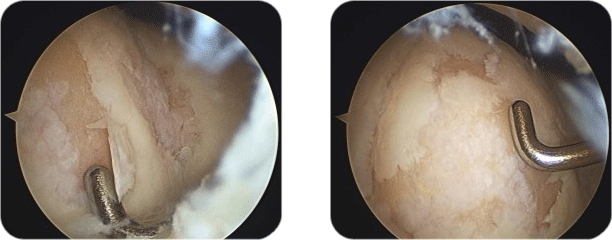

관절 줄기세포 연골재생 수술은 일반적인 관절경 이후에 슬개건 좌측을 약 4~5cm만 미니절개하여, 내측대퇴과의 연골결손부위를 노출시킨 후 그 상태에서 젤 같은 형태의 줄기세포 치료제인 카티스템을 결손부위에 뿌려서 모양을 잡아주는 간단한 수술입니다.

최소절개하는 이유는 관절경상 흐르는 물이 있으면, 젤 상태의 줄기세포 치료제를 잘 굳히고 모양을 잡아주기 어렵기 때문입니다. 줄기세포 치료의 개념이 아직 잘 잡히지 않아서 복용하는 약이나, 혹은 주사로 되어 무릎부위에 주사하는 제형으로 아는 분들이 있는데 줄기세포 치료제는 성체줄기세포의 배양액을 연골세포로 만든 젤형태의 연골결손치료제입니다.

관절 내시경은 흔한 수술 방법으로 작은 카메라를 삽입하여 관절을 관찰하는 방법입니다. 관절 내시경은 무릎 관절 내부의 영상으로 무릎 안의 문제를 진단 및 치료하는데 도움을 줍니다. 기술적으로는 고해상도 모니터, 카메라를 이용하여 무릎 문제를 치료하는데 가장 효과적인 수술 기구입니다.

관절 내시경은 작은 절개를 통해 시행되게 되며 이 삽입구를 통해 작은 카메라가 달려있는 관절 내시경을 관절 안으로 삽입하게 되며 이 카메라에서 영상을 모니터로 전송하게 되고 이 모니터를 통해 보다 자세히 관찰할 수 있습니다. 손상된 조직을 제거 혹은 봉합하기 위해선 작은 수술도구가 필요하게 되며 이들 도구는 무릎의 반대편에 작은 절개를 통한 삽입구로 삽입되어 사용되게 됩니다.

수술 방법

무릎에 몇 개의 작은 삽입구를 형성하게 되고 소독된 물을 무릎 관절 안으로 주입합니다. 무릎을 부드럽게 하고 시야를 깨끗이 확보하여 더 선명한 영상을 얻을 수 있습니다.

가장 중요한 목적은 관절 내시경을 이용하여 정확한 진단을 하는 것이며 만약 수술적 치료가 필요한 경우 수술 도구를 직접 삽입하여 치료를 동시에 시행할 수 있습니다. 검사 진행은 약 10분 정도의 시간이 소요되며 필요한 수술 시간은 관절 내시경을 통해 보이는 손상 정도나 치료 방법에 따라 달라지게 됩니다.